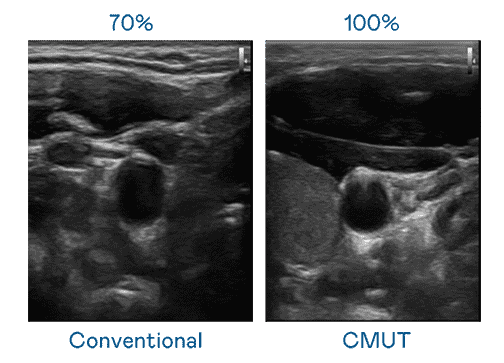

CMUT 技术是一种用电容式微机电元件来产生超音波讯号的技术。。。。与传统 PZT 压电式技术相比,,,CMUT 频宽增加 30%,,更宽频的超音波讯号让影像解析度大幅提升,,,是实现高影像品质医疗超音波扫描、、、、促进精准医疗发展的关键技术。。。。

大频宽带来超清晰影像

超音波影像的解析度高低,,首先取决于探头能发出的讯号频宽。。。。巨星国际 CMUT 可提供高清晰的超音波讯号,,,,提供高频宽、、高灵敏度、、、影像纹理细节更高的超音波影像,,,,协助医护人员缩短影像判读时间及利用精准的医疗影像进行诊断。。。